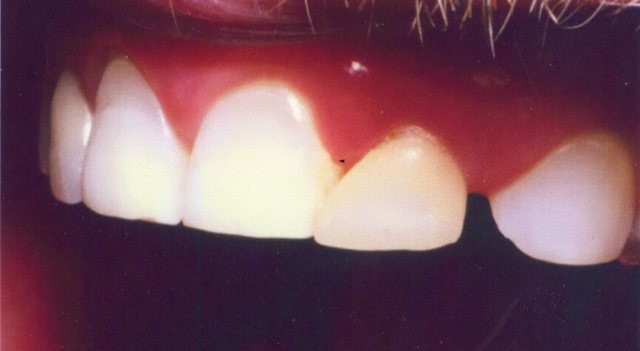

Περιστατικό 1 | Περιστατικό 2 | Περιστατικό 3 |

Περιστατικό 1 | Περιστατικό 2 |

Περιστατικό 1 | Περιστατικό 2 | Περιστατικό 3 |

Περιστατικό 1 | Περιστατικό 2 |

Περιστατικό 1 | Περιστατικό 2 |